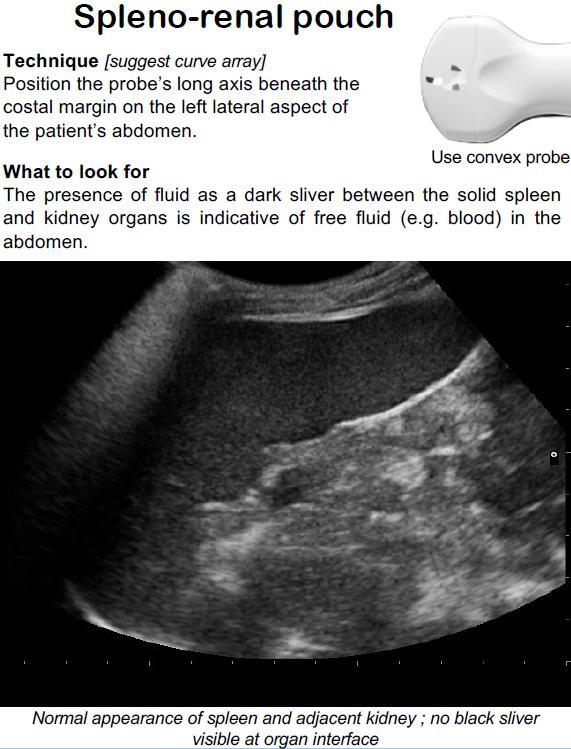

Comparison of Commonly Carried Liquids Against Commercial Ultrasound Gel for Use in the Backcountry Setting

A noninferiority study compared 9 products to commercial gel. Each substance was independently tested on 2 subjects by 2 sonographers covering 8 standardized ultrasound windows. Clips were recorded, blinded, and independently graded by 2 ultrasound fellowship-trained physicians on the ability to make clinical decisions and technical details, including contrast, resolution, and artifact. A 20% noninferiority margin was set, which correlates to levels considered to be of reliably sufficient quality by American College of Emergency Physicians' guidelines. The substances included water, soap, shampoo, olive oil, energy gel, maple syrup, hand sanitizer, sunscreen, and lotion.

CONCLUSIONS

Of the 9 substances tested, 8 were noninferior to commercial gels for clinical decisions. Our study indicates that several POCUS gel substitutes are serviceable to produce clinically adequate images.